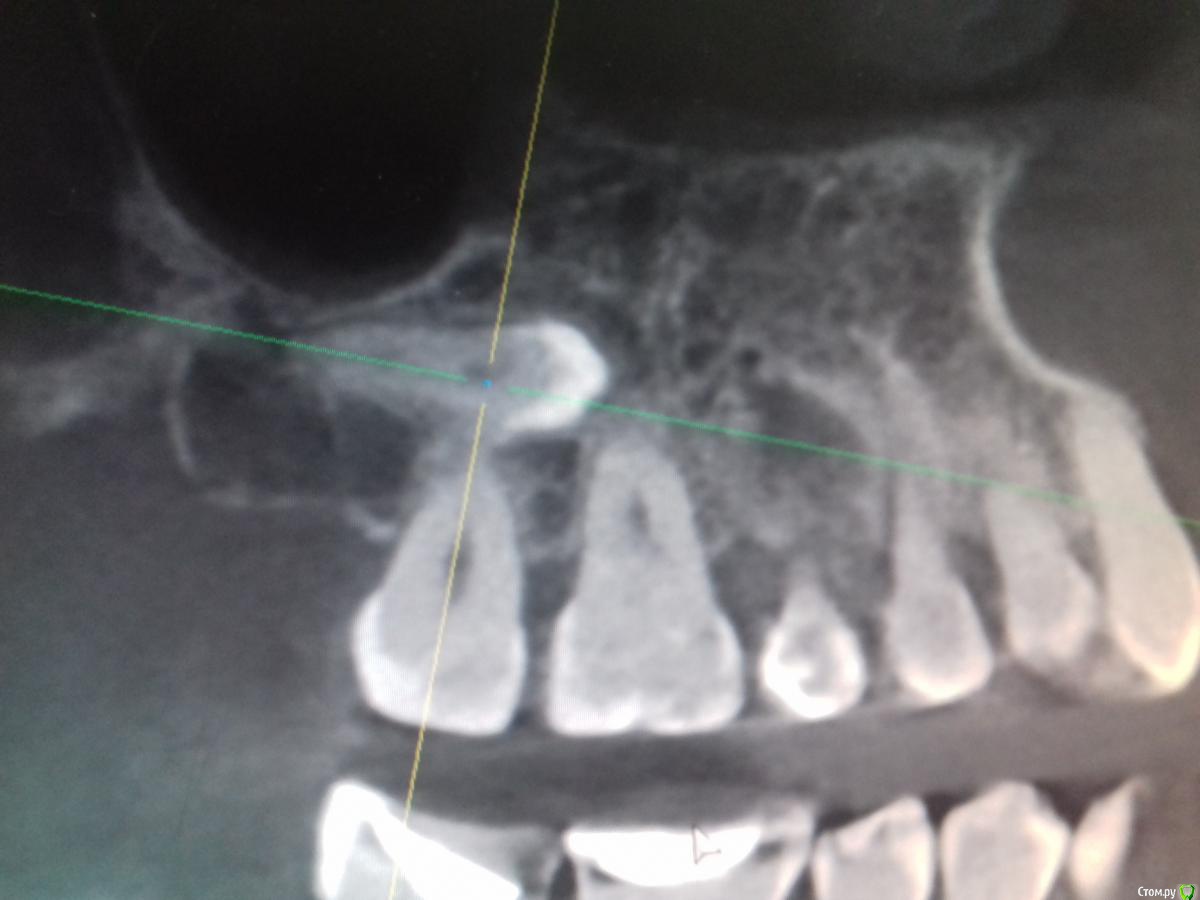

Jurai Опубликовано 29 декабря, 2016 Поделиться Опубликовано 29 декабря, 2016 А эта восьмерка спряталась лучше всех 1 Ссылка на комментарий

diesel87 Опубликовано 30 декабря, 2016 Поделиться Опубликовано 30 декабря, 2016 А эта восьмерка спряталась лучше всехIMG-20161228-WA0002.jpegIMG-20161228-WA0006.jpegIMG-20161228-WA0004.jpegСерьезно легла, убирать будете? Ссылка на комментарий

Jurai Опубликовано 30 декабря, 2016 Поделиться Опубликовано 30 декабря, 2016 А зачем, это случайная находка. Пусть лежит. 1 Ссылка на комментарий